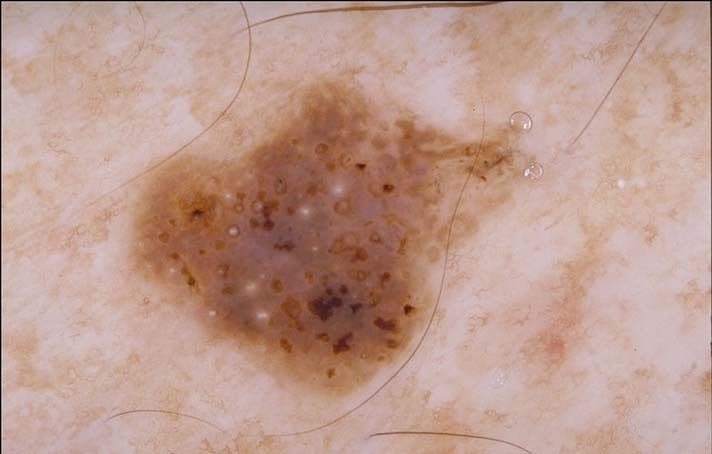

- Melanoma ?

Melanoma ?